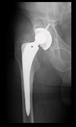

The direction of the cup stem was determined by the guide wire. The aiming device was needed to introduce this wire. After removing the aiming device, the next step was the drilling. Since a cannulated drill bit was used, the previously installed wire could guide the process. A self-positioning reaming tool was then used in the drilled channel. In the prepared cavity, the cup was fitted perfectly. Of the two stemmed cups available to us, the McMinn cup (Waldemar Link, Hamburg, Germany) had the simpler geometry and was therefore chosen. The stemmed cup was inserted according to the manufacturer’s recommendation. In the presence of a significant bone defect, a synthetic bone graft may be impacted for substitution.

The radiological examination allowed us to verify the close bone-to-implant contact and the unchanged position of the implant during follow-up.

In all the cases operated with the above-described targeting procedure, the stems of the cups remained between the cortical bone surfaces without perforation of the linea terminalis, as shown by postoperative radiographs. There were no complicated surgical situations. In 16 cases, the wound healings were uneventful, and the hips were able to bear weight again after postoperative rehabilitation.

At the time of the manuscript edition, some cases reported in this study were still in the early postoperative period. Even the shortest 10-month follow-up means that patients’ wound healing was uninterrupted, and the implant was securely fixed. By this time, patients are beyond successful rehabilitation. Of course, as with all such patients, monitoring will continue at annual check-ups. Report on the mid and long-term outcomes, gait analysis, and subjective assessments of patients is planned.